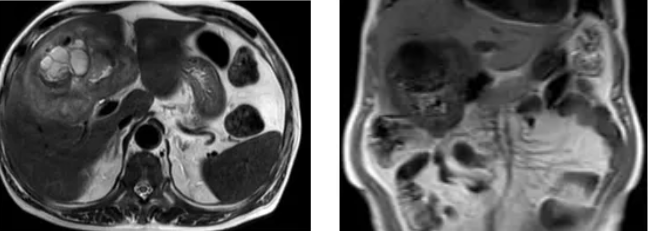

▲ MRI显示胆囊癌并结肠瘘

结合4个月前外院"胆囊癌结肠瘘"诊断,最终行胆囊+部分肝脏+结肠切除术,术后恢复良好。